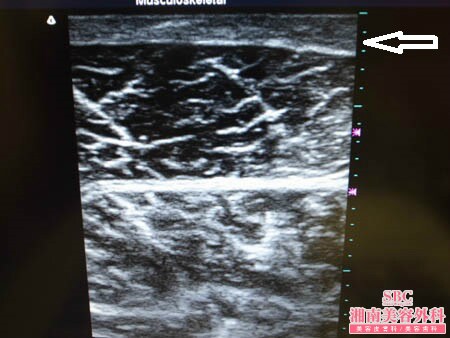

まずはいつものように3Dタッチビュー(=超音波)で

皮下脂肪層をチェックしてみましょう。

手術直前と直後の比較写真になります。

白い矢印部分が皮下脂肪層です。

皮下脂肪層は紙一枚のように薄くなりました。

しかも3Dタッチビューを用いれば

術直後にこの状態を目で見て確認できますので